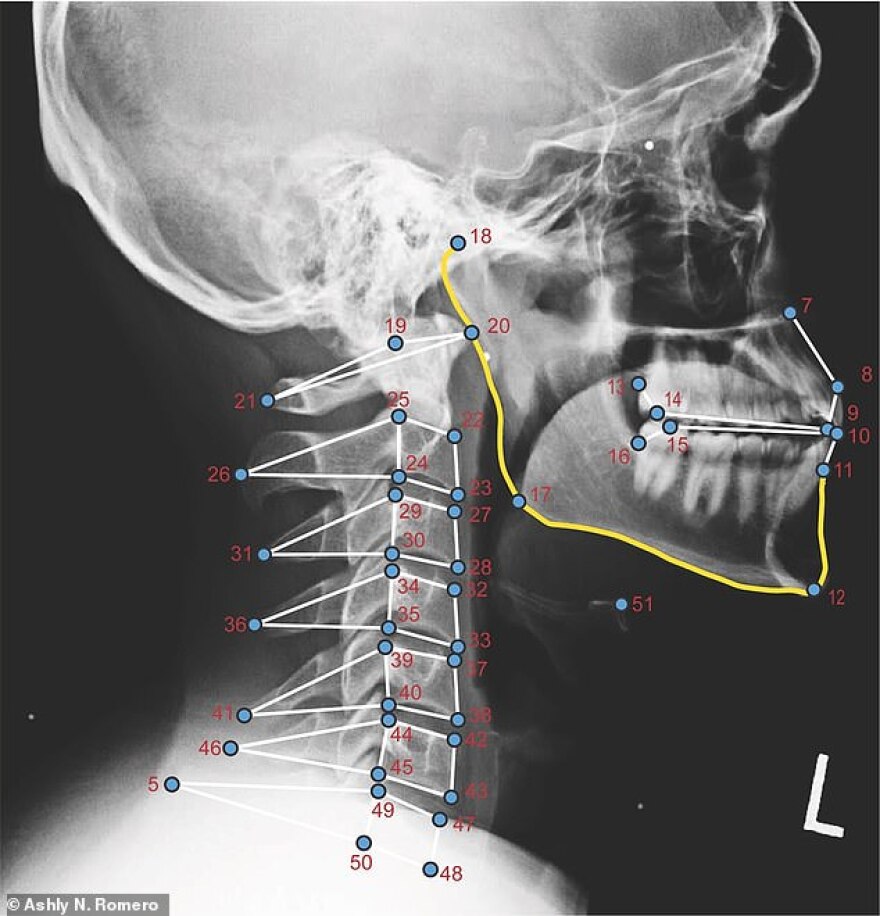

Στο συμπέρασμα αυτό κατέληξαν ερευνητές που μελέτησαν ακτινογραφίες χρηστών ηλεκτρονικών συσκευών.

Οι ακτινογραφίες έδειξαν ότι άνδρες και γυναίκες δεν έχουν διαφορά στις κινήσεις του αυχένα όταν κοιτούσαν στο κέντρο του tablet στο χέρι τους αλλά αυτό αλλάζει όταν οι άνθρωποι κάθονται όρθιοι και γέρνουν στις 15 ή τις 30 μοίρες.